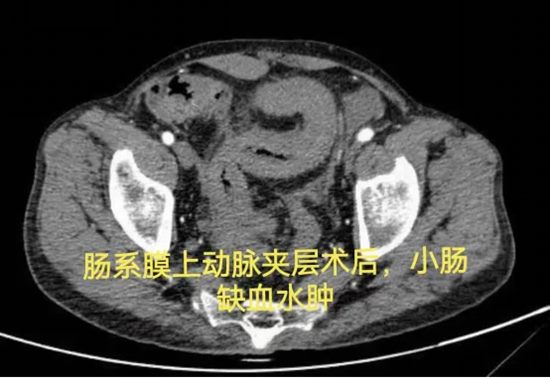

病情简述:53岁男性,肠系膜上动脉夹层术后出现复杂肠瘘,经历三次手术仍无法愈合,入院时白蛋白仅15.0g/L(严重营养不良)。

诊疗破局:面对再次手术的高风险,团队决定“先退一步”,将治疗重点转向营养支持。经过长达3个月的肠内联合静脉营养强化治疗,待患者身体状况改善后,再成功施行“腹腔镜肠粘连松解、瘘口小肠切除+远端回肠及回盲部结肠切除术”,最终成功康复。